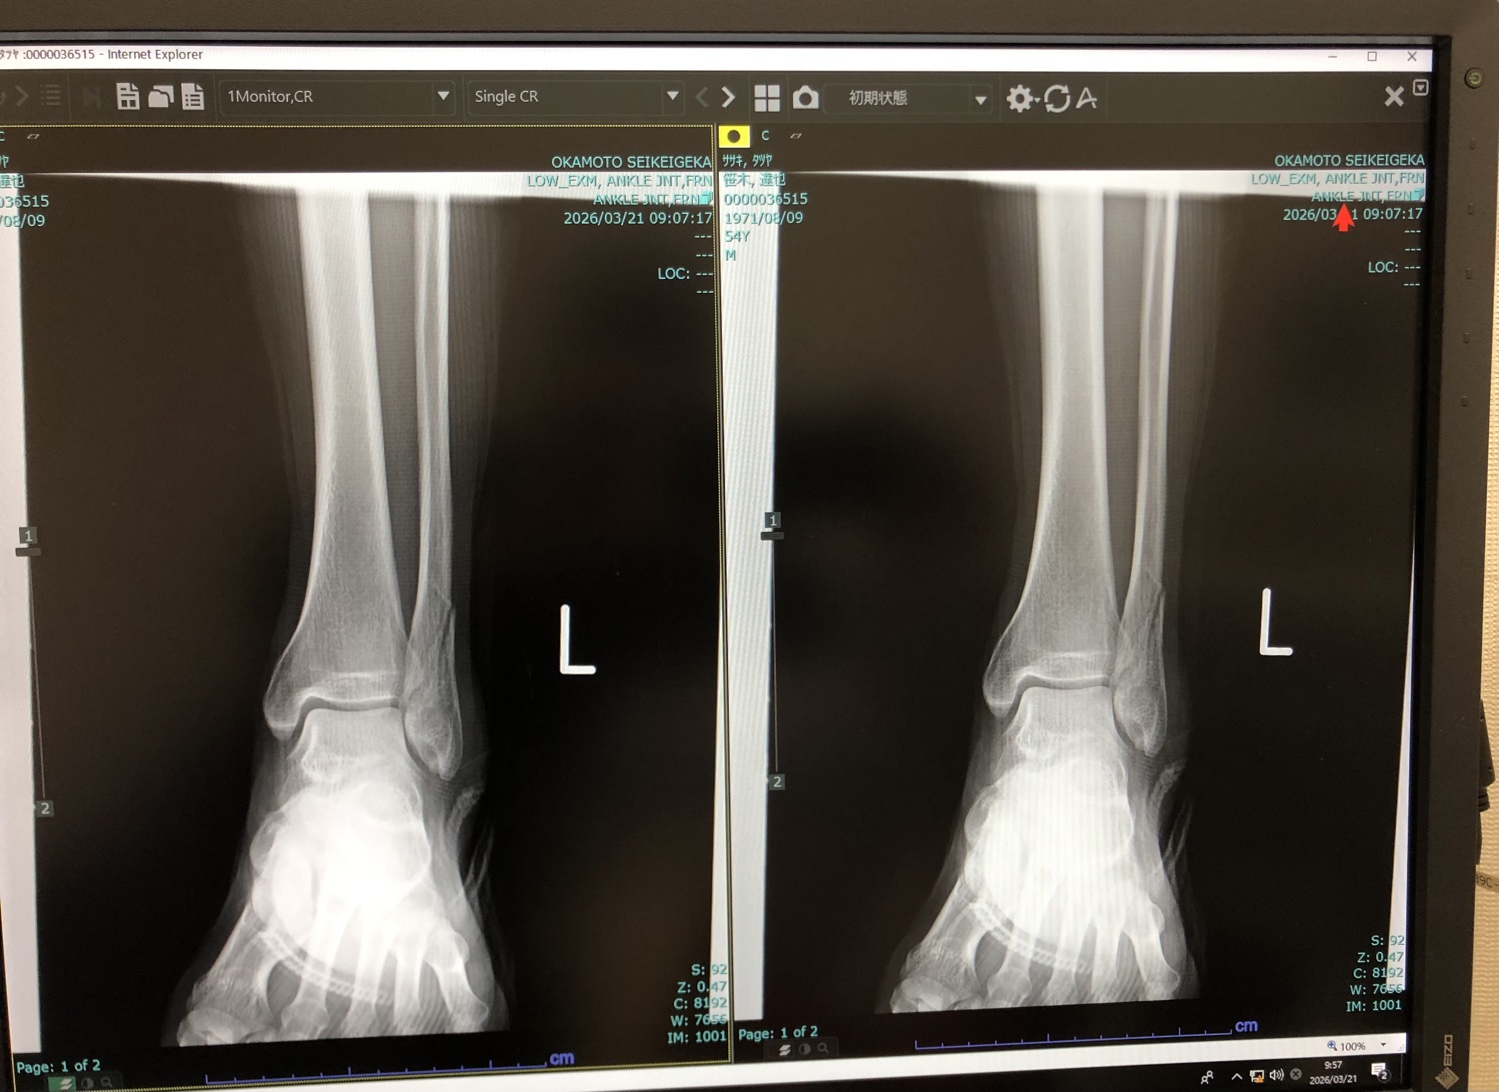

さて、私の足の具合ですが、まだ骨はくっ付いていないんですが、リハビリの成果は確実に出ています

松葉杖を使わなくても、歩けるようになりましたぁ